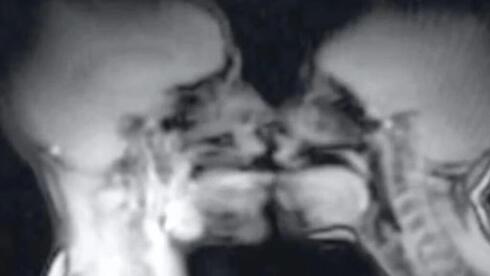

In 1991, a woman and her partner entered an MRI scanner and had sex in the name of science. More than three decades later, the images captured during that experiment, which reshaped medical understanding of human anatomy during intercourse,…